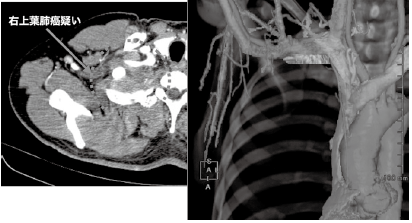

2つ目の症例は、右肺尖部腫瘍に対して、鎖骨下動脈・静脈と腫瘍の位置関係把握目的の検査である。この症例は170cm、70kgの男性であり大柄な体型であった。この検査をEmotion16で実施するには、ポジションと造影条件の工夫が不可欠と考えた。肺尖部は、体幹部を撮影する場合、最も線量を必要とする場所である。よって、しっかりと手を挙上させることで、高速撮影を実施したとしても、線量不足に陥ることを防げる。次に造影条件は、2段階に分けて造影剤を注入することにした。胸部領域においては、通常450mgI/kgの造影剤量で実施している。370mgI製剤だと70kg鎖骨下動脈を通常85mL使用することになる。100mLシリンジを用いると残量は15mLとなり、15mLで胸部領域のCTangiography は困難と判断した。130kVから110kVに管電圧を下げ、造影剤の感度を約20%向上させることで、先行の静脈を濃染させる造影剤量は85mLから20%削減して70mL、CTangiographyに30mLの造影剤を使用することにした。結果的には、1段階目の注入を2mL/s、70mLで注入して注入終了後15秒後に3m/s、30mLで2段階目の注入を行った。これにより、鎖骨下静脈と動脈の間に、CT値が生じ、3D作成を容易にし、血管を区別して作成することが可能となり、依頼医の要望に即した画像提供が可能となった。臨床画像を図4に示す。